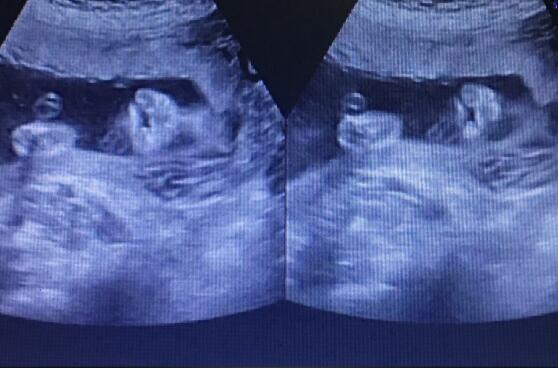

5月12日,正值母親節(jié),本是象征著愛意和美好的一天,但孕21周的二胎孕媽黃女士在武漢仁愛醫(yī)院做四維大排畸檢查時(shí)卻收到了一個(gè)晴天霹靂。 胎兒嘴唇上有裂縫,為唇裂?!ぁぁ?/p> read more